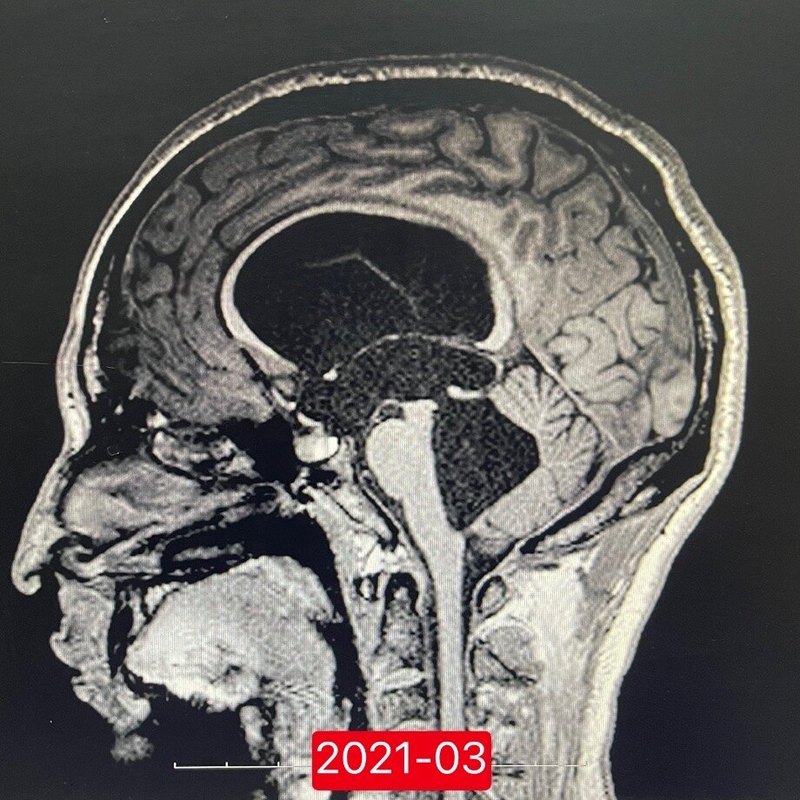

近兩日我們兩年前手術(shù)的一個患者來門診找肖主任復查。圖1這樣的片子拿到很多地方,都會被說腦室系統(tǒng)全部增大,交通性腦積水,需要分流治療??墒俏覀冊傧胍幌?,死摳教科書上的定義對于治療真的有意義么,第四腦室流出道的外部或者枕大池的部分粘連會不會引起腦脊液流出不暢進而全腦室擴大?那么這種情況,根據(jù)教科書的定義,你要叫他交通,可是事實上蛛網(wǎng)膜下腔的部分粘連何嘗不算是梗阻的一種形式呢?圖2是昨天復查的磁共振片子,我們可以明顯看到在進行第三腦室底造瘺術(shù)后接近兩年的時間,第四腦室擴張縮小、小腦受壓改善、中腦頂蓋部上抬改善,原本第三腦室底部的下疝也變得平坦,患者本人也覺得講課時候思考的能力也變強了。對于這位患者,我們在鏡下看到可疑既往腦炎的改變,炎性反應引起部分蛛網(wǎng)膜下腔的粘連。同樣類似類型的問題,后顱窩術(shù)后出現(xiàn)的腦積水,第四腦室流出道粘連導致的腦積水,囊蟲卡在枕大池里,這都是教科書里沒辦法逐一寫清楚,又確實存在的問題。這一類患者,分流行不行,當然行;不分流有沒有機會,也會有。